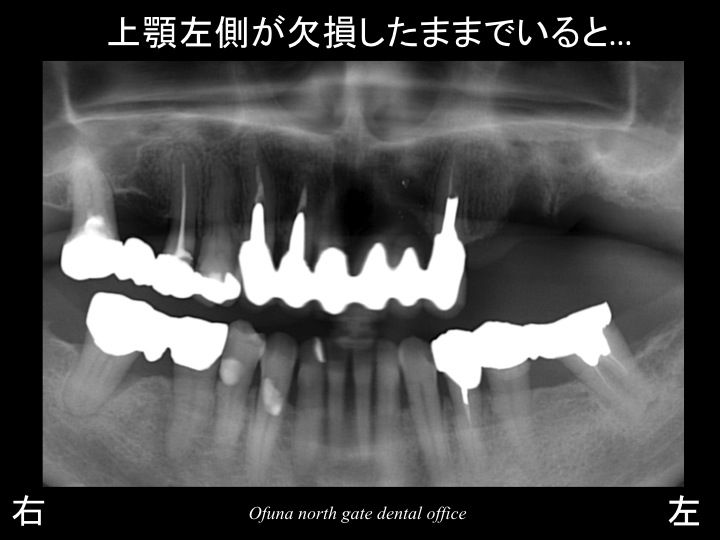

問題なのは、抜歯後です。

抜歯したままでいるとさまざまな問題が起こります。

上顎左側で噛めない分、噛む力が残っている歯に加わりやすいのです。

特に上顎前歯部は、

神経がない!

ブリッジとなっている!

ということから今後のことを考えれば、歯根破折となり ダメ(抜歯)となる可能性があります。

つまり、上顎左側の奥歯が欠損しているままであると

将来的には上顎前歯部もダメになりやすいということです。

将来性を考えれば、上顎左側はきちんと噛めるようにすることが必要です。

そこでインプラント治療を検討します。